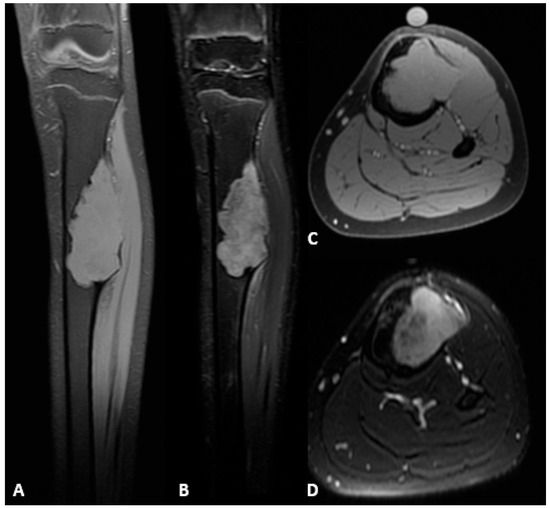

Background: Reconstructing large bone defects in pediatric patients after tumor resection is challenging, as conventional techniques are associated with high complication rates and morbidity. The Intramedullary Bone Transport Nail (IMBTN) may reduce these complications while preserving limb alignment and skeletal growth in pediatric oncologic reconstruction. Methods: A 15-year-old female with an osteofibrous dysplasia-like adamantinoma of the tibial diaphysis underwent complete en-bloc resection, leaving a 9 cm bone defect. An IMBTN (Precice, NuVasive) was implanted for distraction osteogenesis, with distraction starting eight days post-surgery at 0.25 mm twice daily. Follow-up visits monitored bone healing, alignment, and limb length. Results: The 9 cm defect was successfully reconstructed, with complete bone healing at the distraction site. Complete consolidation was confirmed at 18 months. The transport nail was removed at two years, and no further revisions were necessary. At two-year follow-up, the patient reported minimal pain on the Visual Analog Scale 1/10, and no recurrence of the tumor was noted. Conclusions: The use of IMBTN for large bone defect reconstruction following tumor resection in pediatric patients is a safe and effective technique. It enables stable bone transport while preserving alignment, maintaining limb length, and is less invasive than traditional reconstructive approaches. Full article

Figure 1